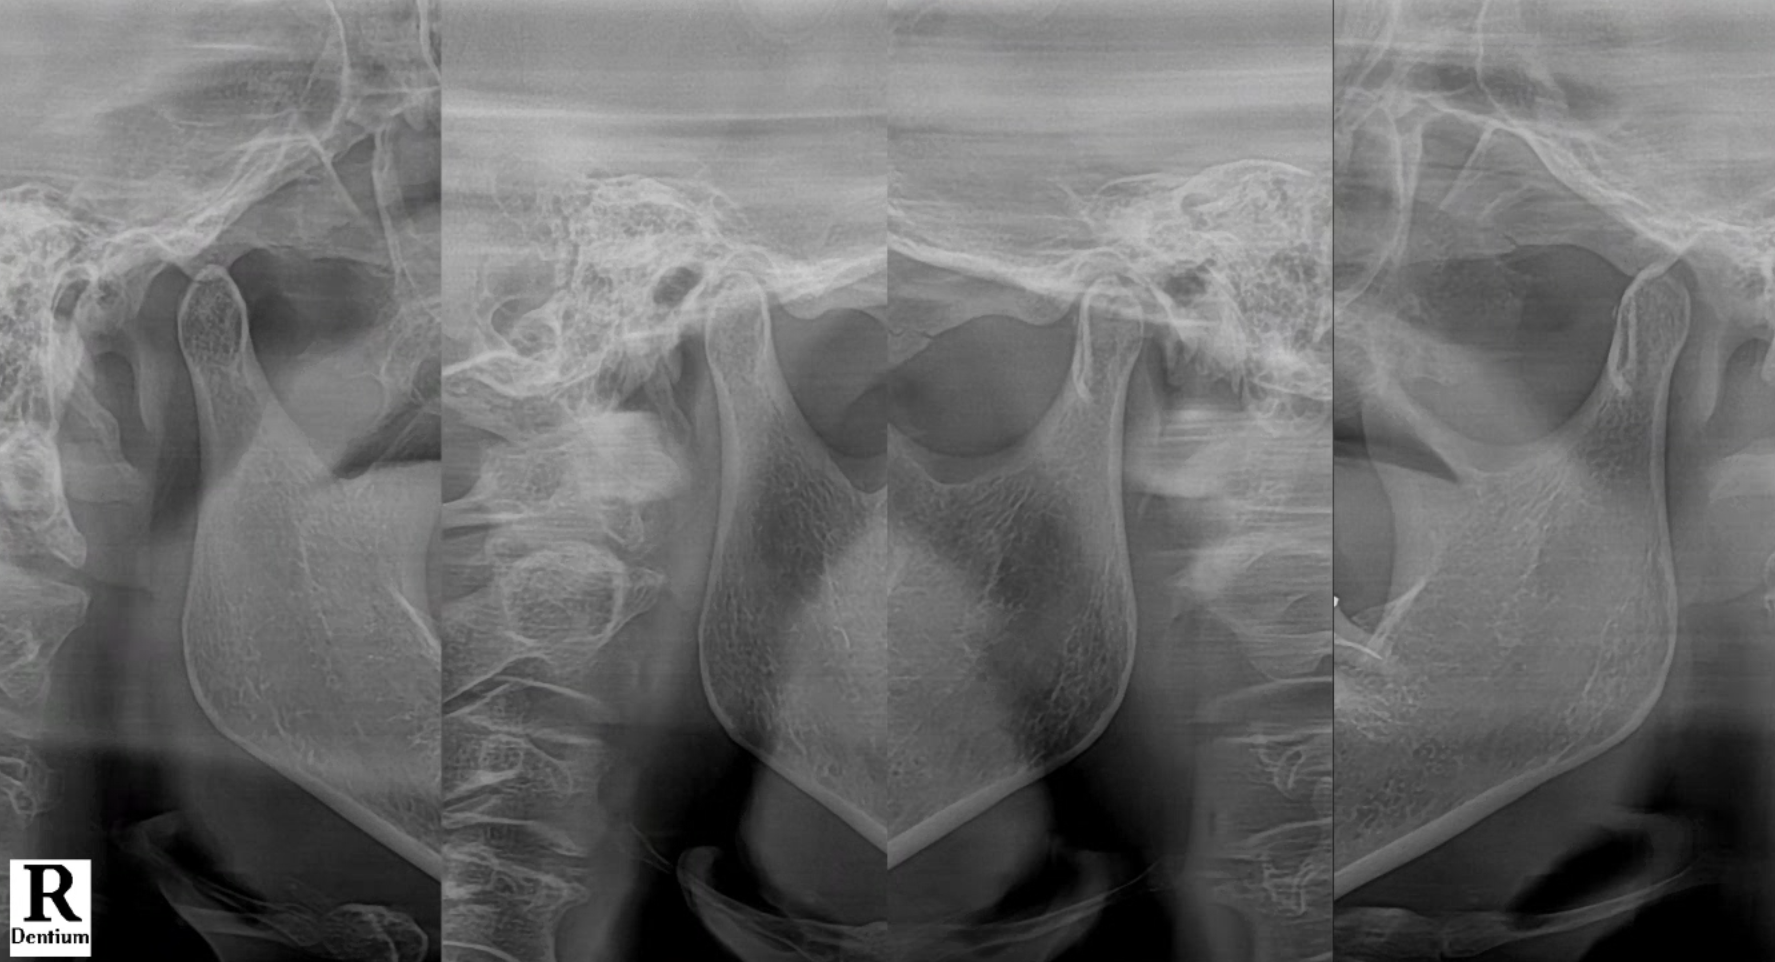

Why Does TMJ Cause So Many Symptoms?

The temporomandibular joint is a small but powerful joint, used all day for chewing, speaking, and even yawning.

When it becomes strained or inflamed, it affects the surrounding nerves and muscles.

That’s why patients often feel pain in the ears, teeth, head, or neck, even though those areas are completely healthy.

The real problem lies in the TMJ.